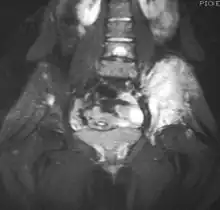

Extraskeletal Ewing sarcoma hard palate

Top: Ewing sarcoma of the thigh bone on a child's CT scan

Bottom: Extraskeletal Ewing sarcoma of the hard palate